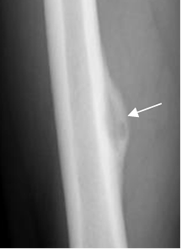

Fig 38. Reacción perióstica benigna.

Rx AP. Reacción perióstica continua, en un osteoma osteoide.